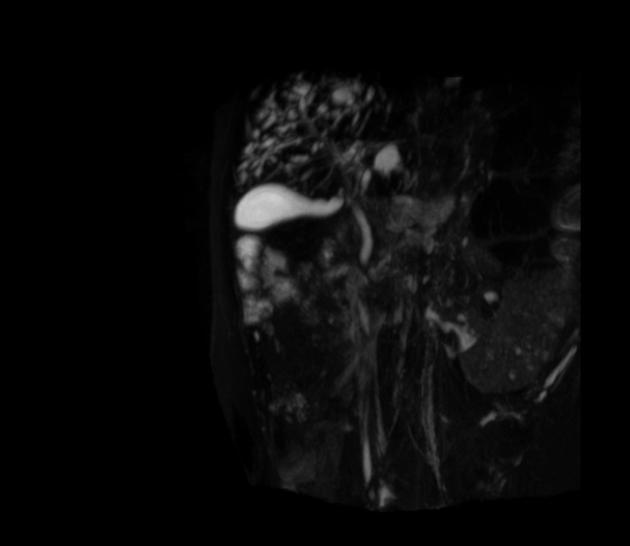

Caroli disease (todani type V) plus ADPKD

caroli disease (todani type V)

mesh of small bile ducts in the liver parenchyma draining into gallbladder